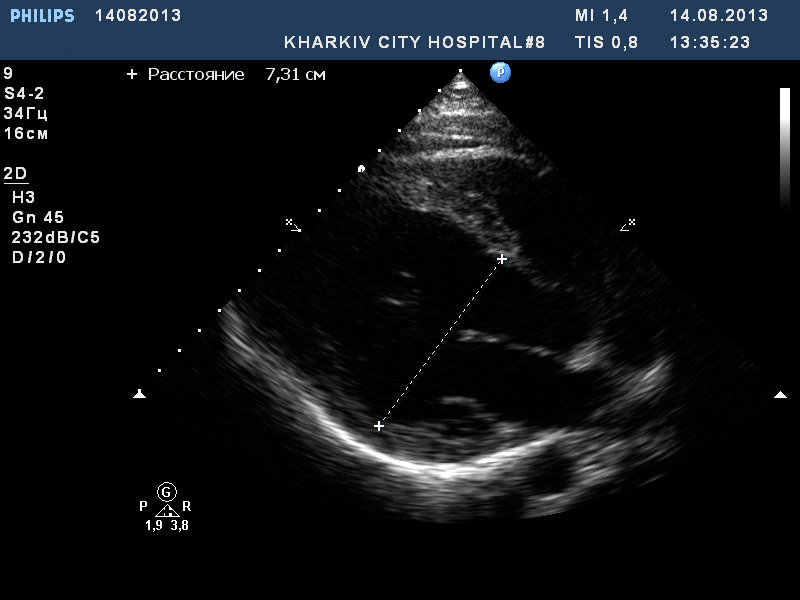

Молодой парень, спортсмен-боксер, на чемпионате в момент сильной физической нагрузки (плюс отмечает что получил сильный удар в область сердца)почувствовал себя плохо. Через время пришел амбулаторно сделать ЭКО-КС. Увидел такую ситуацию: двухстворчатый аортальный клапан с пролабированием и регургитацией, при чем по короткой оси не могу исключить отслоение интимы. дилатирован левый желудочек до 6,4 в диастолу. Рекомендовал консультацию кардиохирурга. Это было полгода назад. Пришел вчера. полость ЛЖ 6,7 в диастолу. Он еще и продолжал тренироваться эти полгода. К кардиохирургам не ездил. Приходил с отцом, у отца мнение, что все что у сына ничего страшного. Внешне сын атлетически сложен, жалоб на момент осмотра нет, как результат отец недооценивает ситуацию. Все таки, думаю, убедил ехать к кардиохирургам. Ваше мнение исходя из некоторых видео.

Пришел сегодня этот парень. Начал чувствовать себя периодически "не очень" . Отмечает перебои в работе сердца. Надумал ехать в Киев к кардиохирургам на консультацию и дальнейшее оперативное лечение.

Левый желудочек расширился до 7.3 см в диастолу.